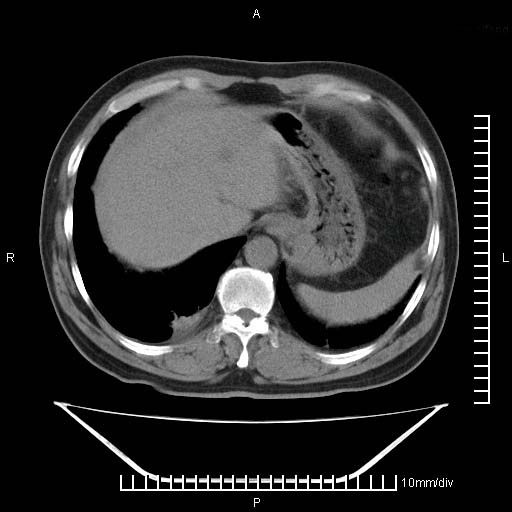

标题: CT25082:肝脏增强:男性,70岁 [打印本页]

标题: CT25082:肝脏增强:男性,70岁

患者以心脏疾病收住院,腹部无明显症状,b超查肝脏有占位。

增强效果不理想。考虑转移,胆囊壁明显增厚,不排除胆囊癌肝转移。

牛眼征,中心坏死无强化,外缘强化,最外缘又见低密度,考虑转移,与脓肿鉴别

考虑右肺下叶周围癌肝转移

肝内多发转移瘤,右下肺炎症并少量胸水。胃壁增厚建议胃镜,胰尾部“病变”为肠管。

1)肝脏多发性转移瘤(不排除胰尾癌转移所致可能)。2)腹水。3)右侧少量胸腔积液。

ct25082 结果:转移瘤

外院mr结果:胰尾恶性占位。